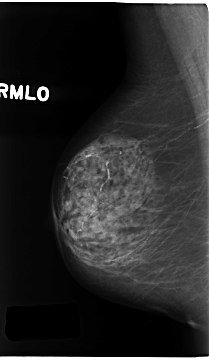

ics_version 1.0 filename C-0196-1 DATE_OF_STUDY 16 9 1996 PATIENT_AGE 83 FILM FILM_TYPE REGULAR DENSITY 2 DATE_DIGITIZED 26 3 1998 DIGITIZER LUMISYS LASER SEQUENCE LEFT_CC LINES 4728 PIXELS_PER_LINE 2536 BITS_PER_PIXEL 12 RESOLUTION 50 OVERLAY LEFT_MLO LINES 4736 PIXELS_PER_LINE 2712 BITS_PER_PIXEL 12 RESOLUTION 50 OVERLAY RIGHT_CC LINES 4616 PIXELS_PER_LINE 2824 BITS_PER_PIXEL 12 RESOLUTION 50 NON_OVERLAY RIGHT_MLO LINES 4672 PIXELS_PER_LINE 2712 BITS_PER_PIXEL 12 RESOLUTION 50 NON_OVERLAY |

FILE: C_0196_1.LEFT_MLO.OVERLAY TOTAL_ABNORMALITIES 1 ABNORMALITY 1 LESION_TYPE MASS SHAPE OVAL MARGINS SPICULATED ASSESSMENT 5 SUBTLETY 5 PATHOLOGY MALIGNANT TOTAL_OUTLINES 1 BOUNDARY |